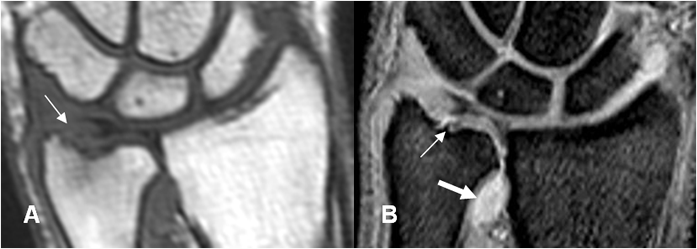

Fig 79 C. Ruptura del complejo del FCT.

A: RM coronal en T1 y B: RM coronal en GE. Líquido en la articulación radioulnar distal, como signo de ruptura del FCT (Flechas delgadas). Hay ruptura del menisco en la inserción radial por lesión tipo 1D. (Flecha gruesa).